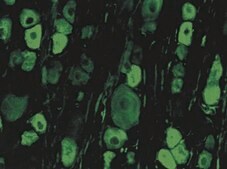

Anti-Internexin Antibody, α is an antibody against Internexin for use in ELISA, WB, IC, IH.

Immunohistochemistry on formalin or paraformaldehyde fixed tissues.

Immunocytochemistry.

alpha-internexin, C-terminal globular "tail" region. By western blot, AB5354 detects a major band at 66 kDa and a minor band at approximately 150 kDa corresponding to alpha internexin monomer and dimer, respectively. A minor band at approximately 50 kDa is occasionally detected and is believed to be a degradation product of alpha internexin. This antibody has been referred to in the literature as the R36 antibody (Evans, 2002).